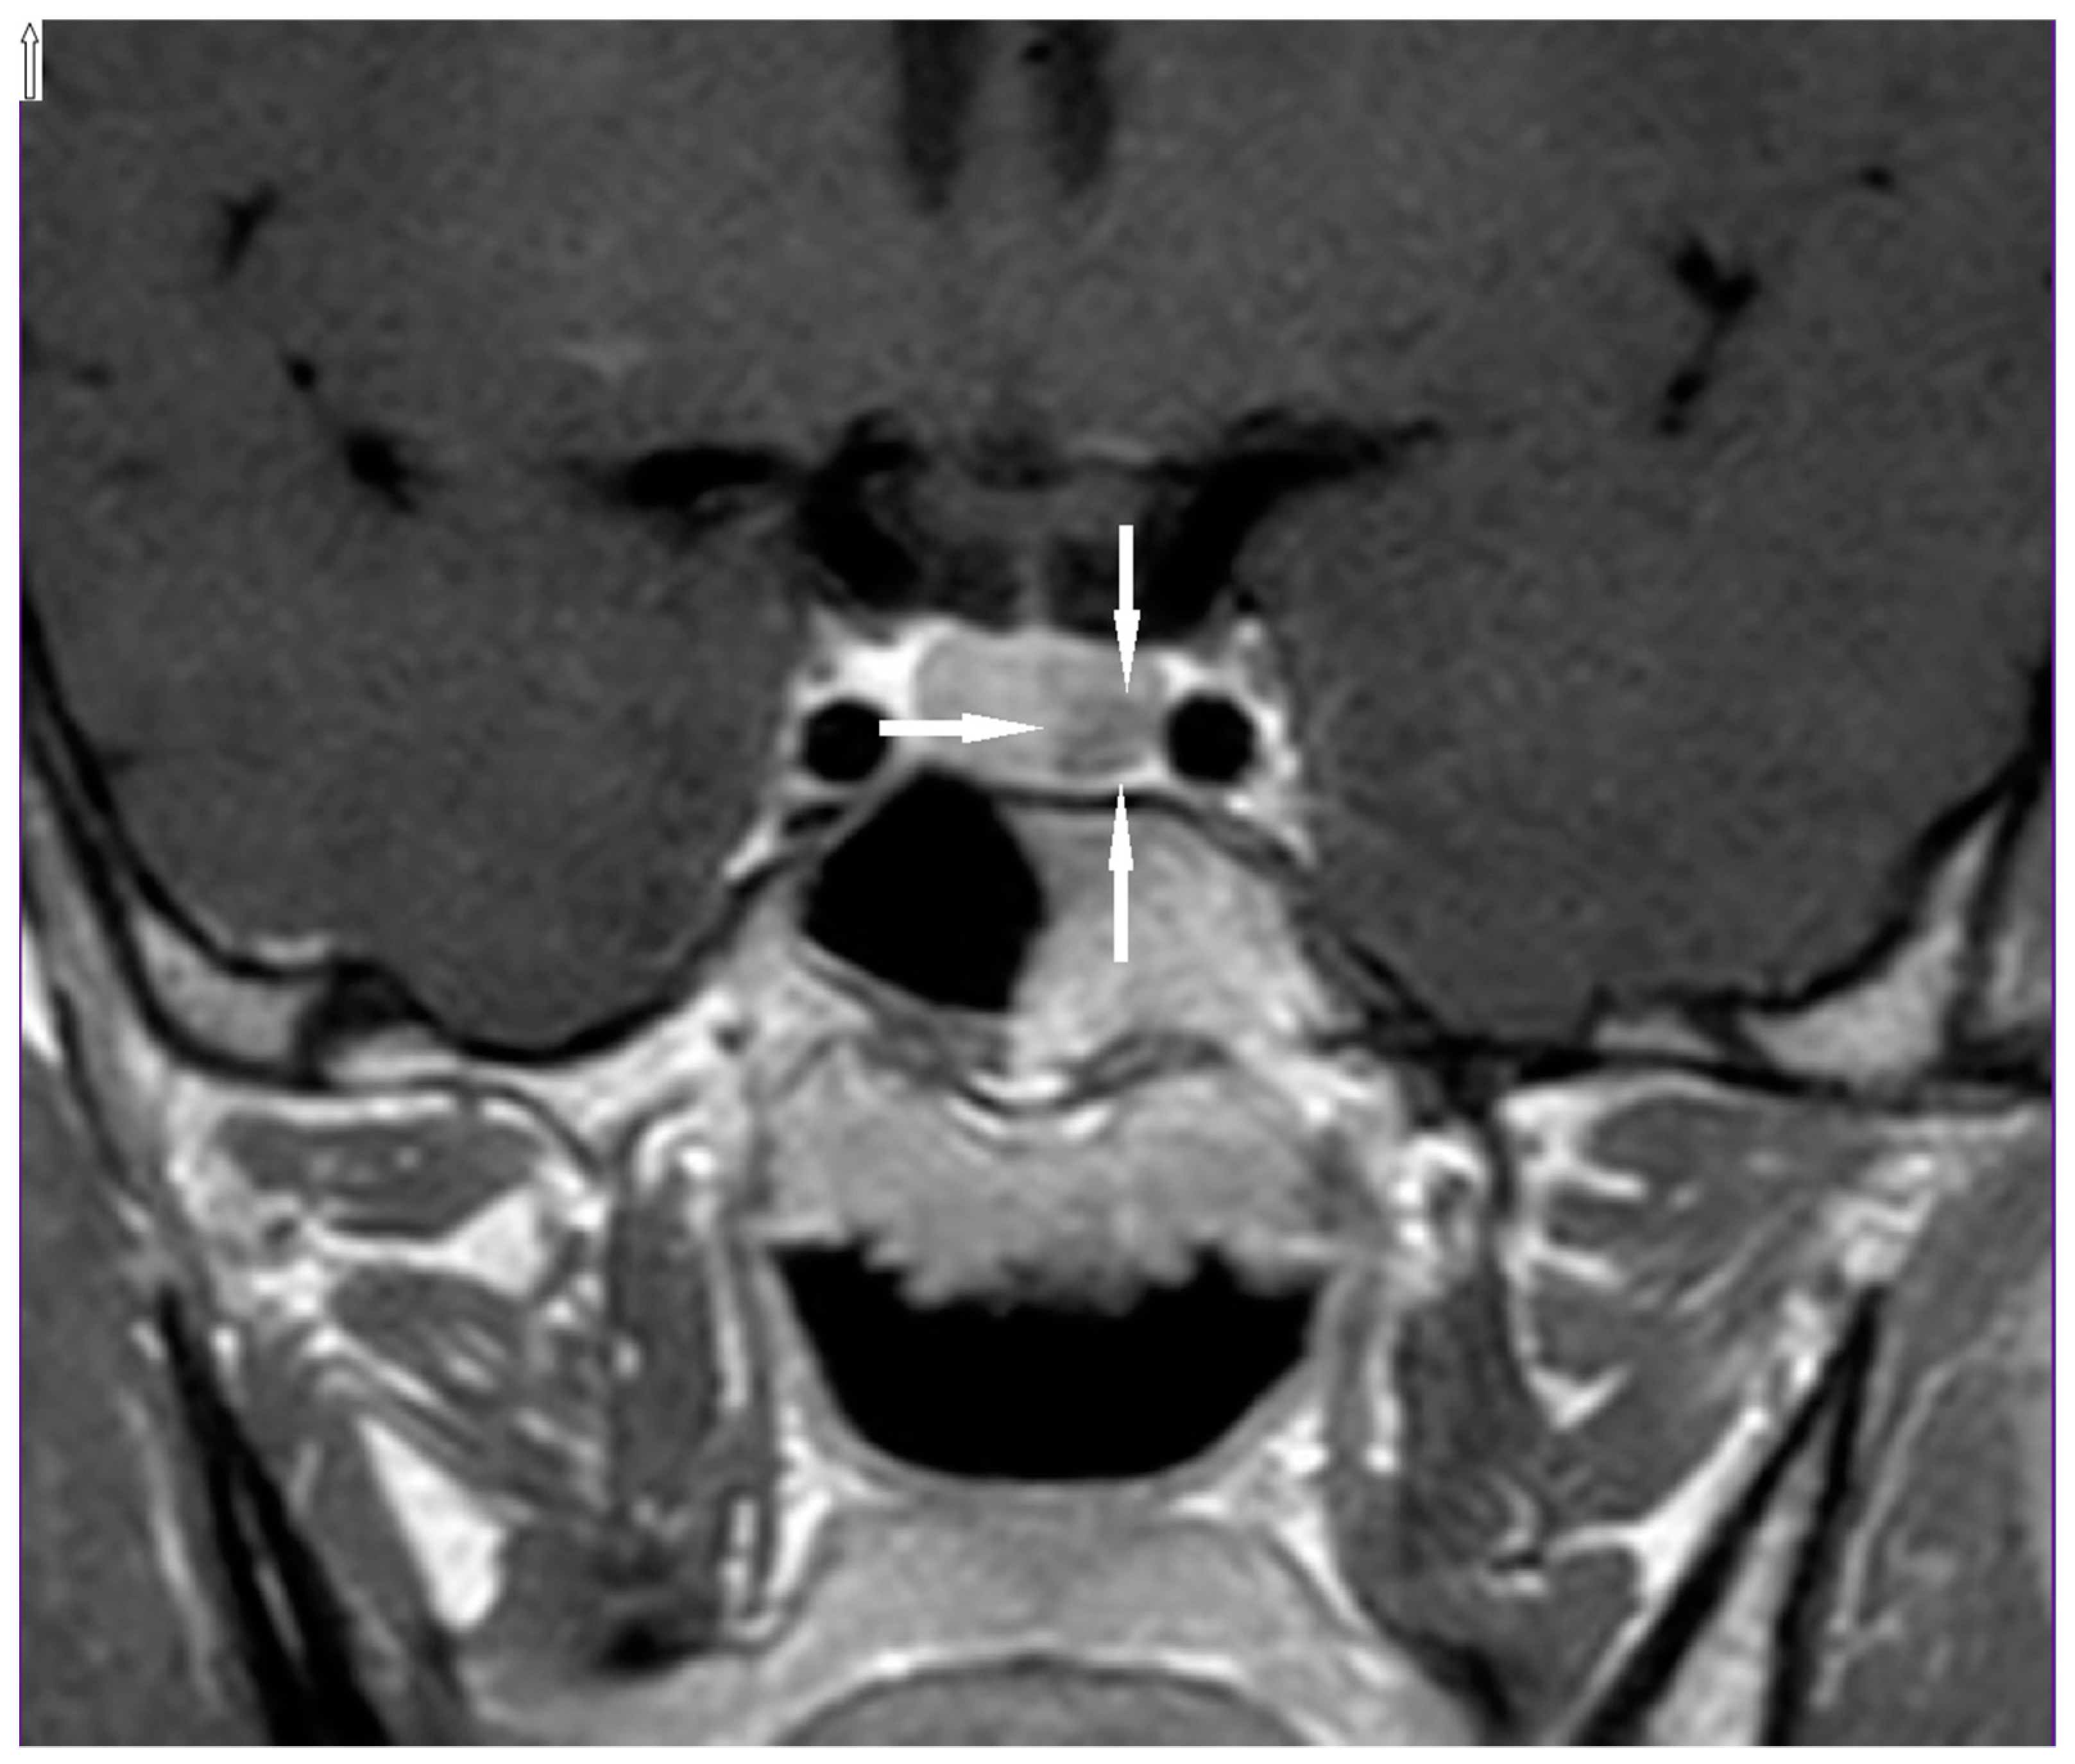

2. Case Presentation

2.1. Patient’s Description